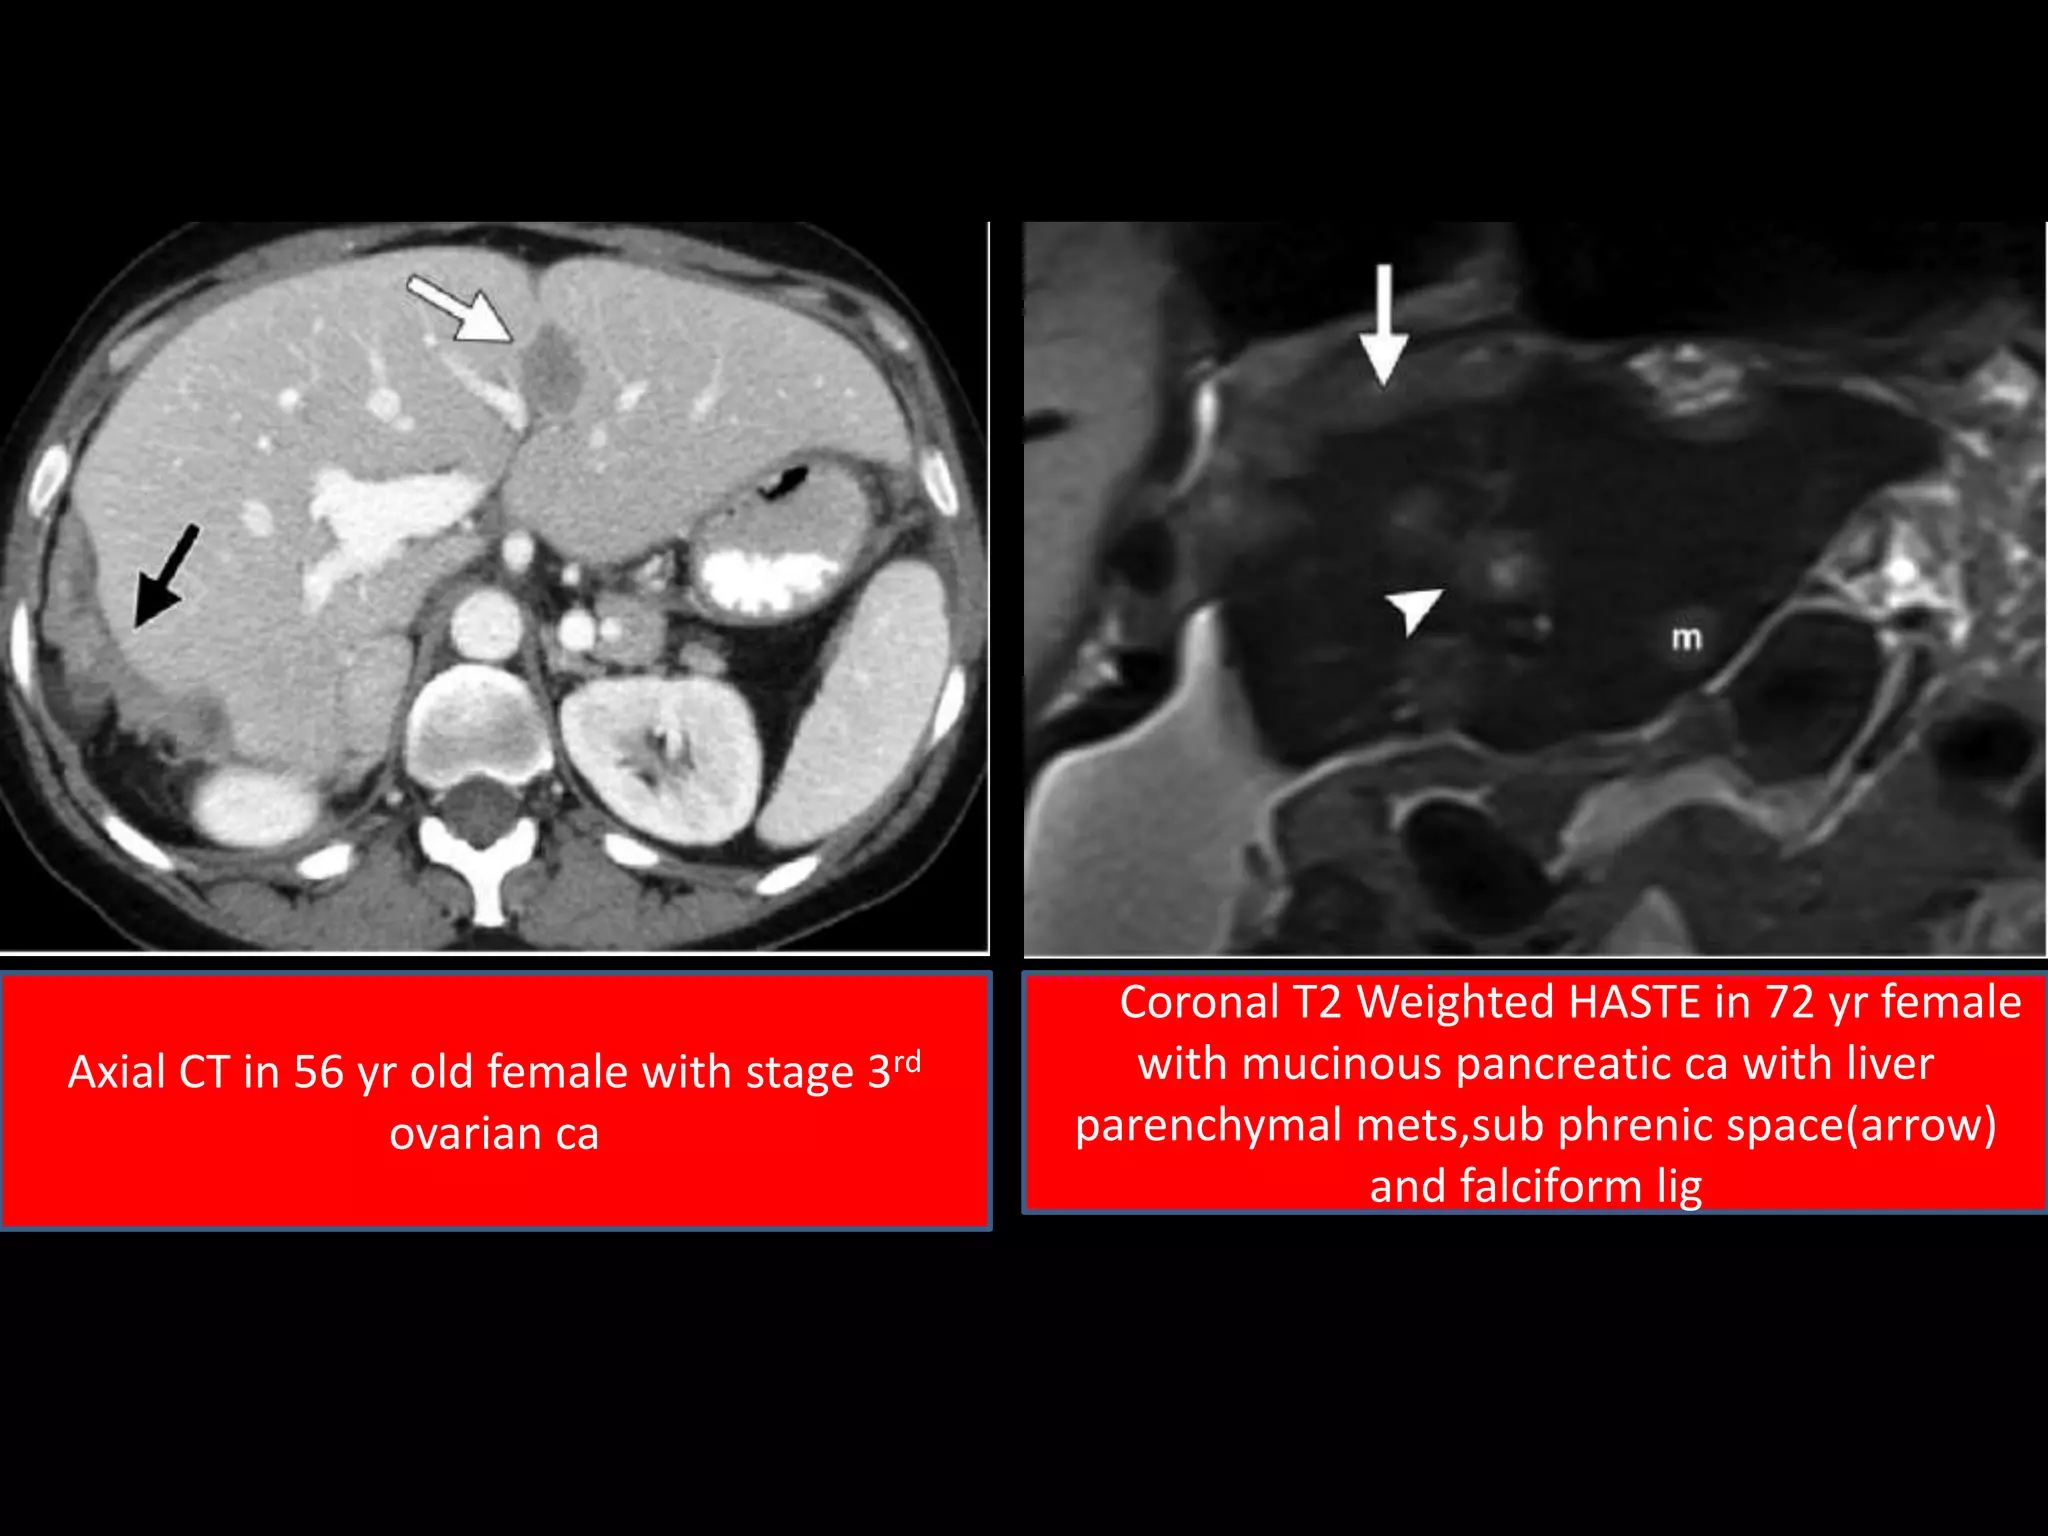

Axial CT in 56 yr old female with stage 3rd

ovarian ca

Coronal T2 Weighted HASTE in 72 yr female

with mucinous pancreatic ca with liver

parenchymal mets,sub phrenic space(arrow)

and falciform lig